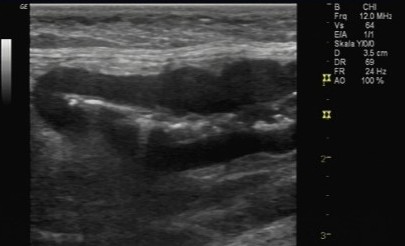

Erkrankungen der Nebennieren

Die Nebennieren sind kleine aber wichtige hormonproduzierende Organe neben den Nieren. Entgegen ihres Namens haben sie mit der harnproduzierenden Funktion der Nieren nichts zutun. Sie sind für die Produktion von Glukokortikoiden, Mineralokortikoiden und Geschlechtshormonen zuständig. Diese Hormone ermöglichen dem Körper eine adäquate Reaktion auf Streß und beeinflußen zahlreiche Stoffwechselfunktionen. Sowohl eine Unterfunktion (Addison) als auch eine Überfunktion (Cushing) führen beim Hund zu schweren körperlichen Einschränkungen.

Ältere Katzen leiden manchmal am sogenannten Coon-Syndrom, einem Nebennierentumor der zu Bluthochdruck und lebensgefährlichem Kaliumverlust führt.